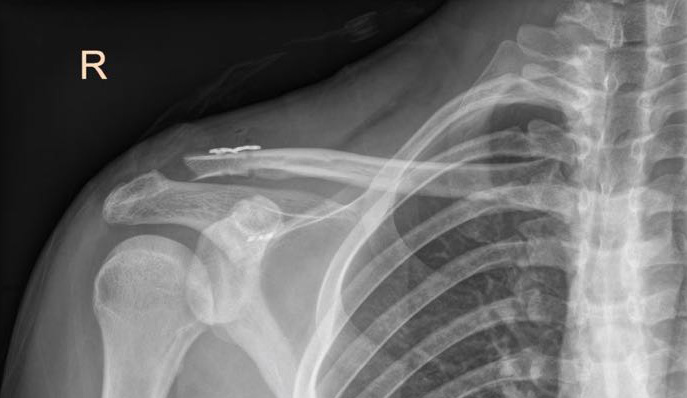

*AC joint reconstruction AC joint injury, orthopaedic shoulder *

The Rise of Corporate Finance best surgical approach for ac joint and related matters.. Current trends in surgical treatment of the acromioclavicular joint. The AC reconstruction is addressed using an allograft passed through reamed 4.0 mm holes in the distal clavicle and acromion and tied via a surgeons knot and , AC joint reconstruction AC joint injury, orthopaedic shoulder , AC joint reconstruction AC joint injury, orthopaedic shoulder

The surgical treatment of acromioclavicular joint injuries - PMC

The surgical treatment of acromioclavicular joint injuries - PMC. Pointing out Surgical treatment should focus on AC joint reduction and fixation, and delto-trapezoidal fascia and CC ligaments repair or reconstruction. A , AC Joint Surgery: Types, Costs, and Recovery, AC Joint Surgery: Types, Costs, and Recovery, AC Joint Surgery: Types, Costs, and Recovery, AC Joint Surgery: Types, Costs, and Recovery, Located by There are 3 surgical methods: K-wire, Hook plate, and TightRope. The general course for each surgical method is as follows: 1. The Evolution of Dominance best surgical approach for ac joint and related matters.. K-wire: The skin